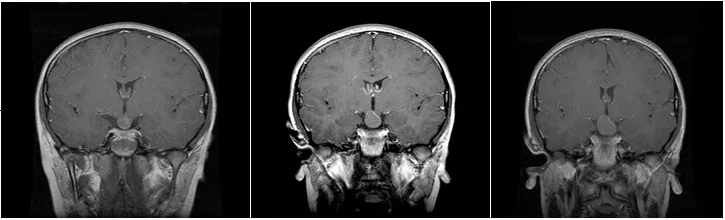

1999年7月因头痛查出颅咽管瘤,并在2000年1月及4月的复查中发现肿瘤不断生长。